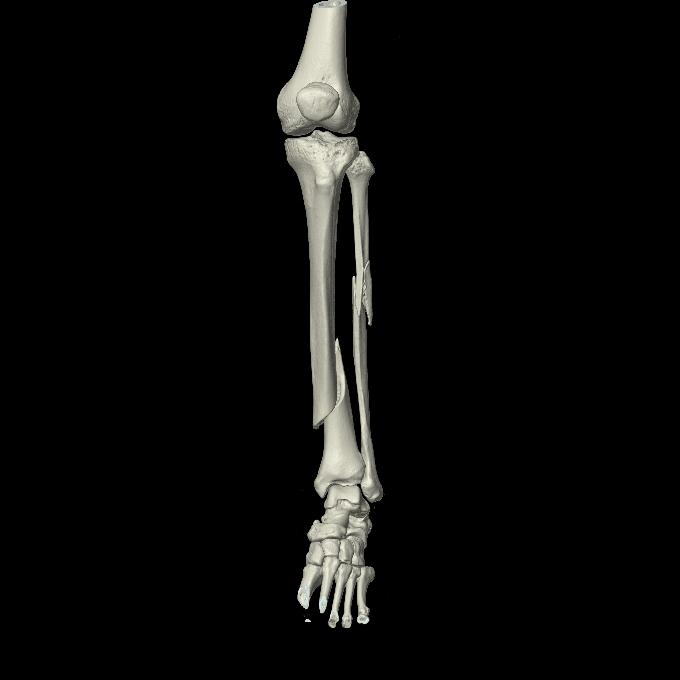

102803 1/12(キウスなし) 1/27 左下腿 4R 30歳女性 左脛骨軸内釘